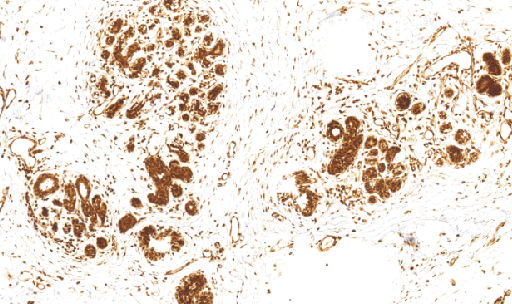

O⁶甲基鸟昔-DNA-甲基转移酶(MGMT)是一种DNA修复蛋白,正常组织常有表达,而肿瘤组织表达低,可能与该基因的甲基化有关,同时也是继发性耐药的一种标记,主要用于结肠癌、星型细胞瘤等各种恶性肿瘤的研究

- 阳性部位:胞核,胞质

- 适用组织:石蜡切片

- 预处理:热修复